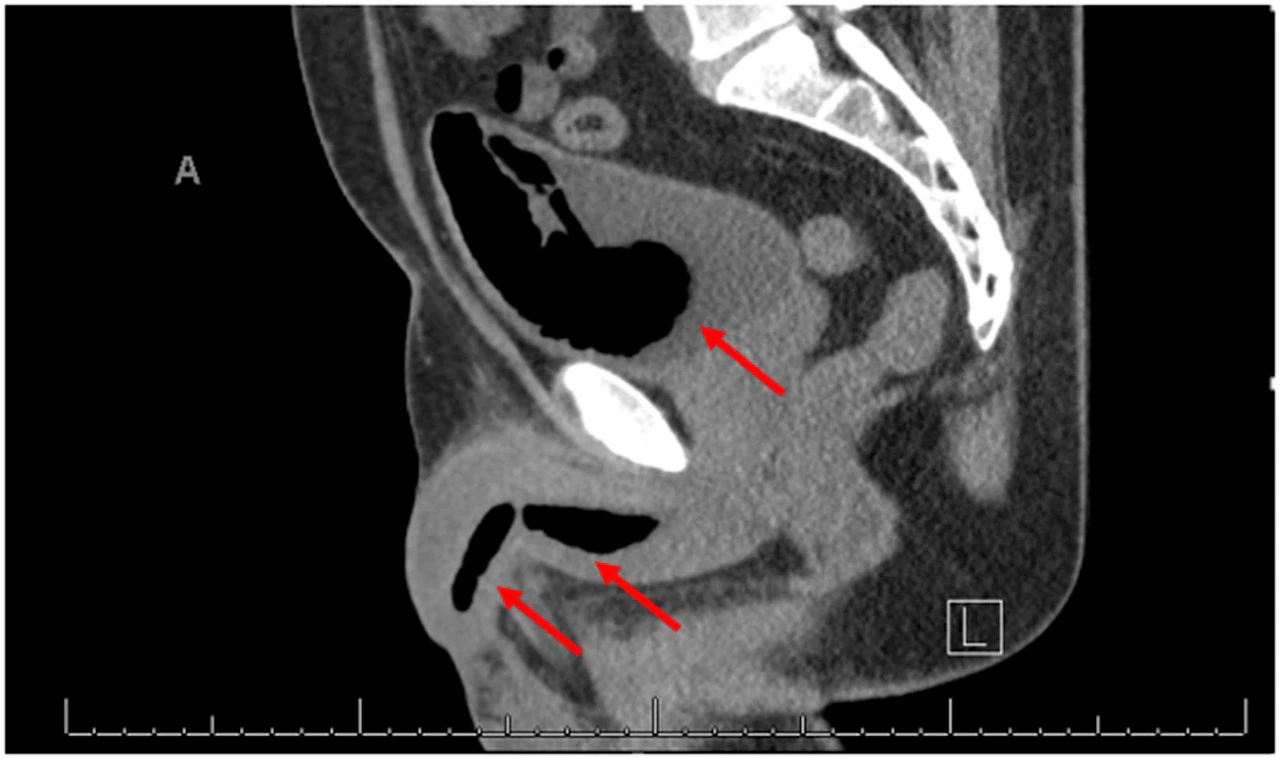

Der Mann hatte über anhaltende Bauchschmerzen geklagt, woraufhin Untersuchungen schließlich einen Fremdkörper im ersten Abschnitt des Dünndarms, dem sogenannten Duodenum, zeigten: ein Thermometer.

Das Gerät hatte sich so im Körper positioniert, dass es direkt gegen die Darmwand drückte. Dadurch bestand akute Gefahr von Verletzungen und inneren Blutungen. Die Ärzte reagierten rasch und entfernten den Fremdkörper im Rahmen eines rund 20-minütigen Eingriffs erfolgreich.

Diese Hoffnung erwies sich als Irrtum. Zwar blieb das Thermometer über all die Jahre offenbar intakt, genau das könnte ihm jedoch das Leben gerettet haben: Enthaltenes Quecksilber hätte im Falle eines Austritts zu einer akuten lebensbedrohlichen Vergiftung führen können.